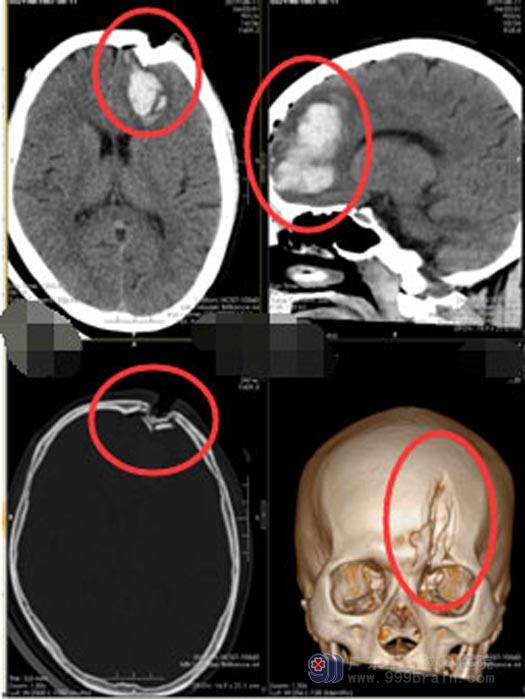

小儿子车祸时生命垂危,在当地医院初步处理后,医生建议立即转上级医院。儿子头部及全身多处损伤,头顶有一个约10cm的伤口,伤口内有粉碎的颅骨,情况非常危急,开通绿色通道后,立即急诊实施“左额叶血肿清除术+额骨凹陷性骨折整复术+硬脑膜修补术”。天亮时,手术成功地结束了。

▲手术前